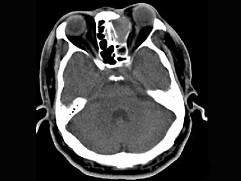

男,34岁,头痛、头晕3个月余,CT检查如图,最可能诊断为 ( )

• A.筛窦炎

• B.筛窦黏液囊肿

• C.筛窦息肉

• D.筛窦乳头状瘤

• E.筛窦癌

答案: B